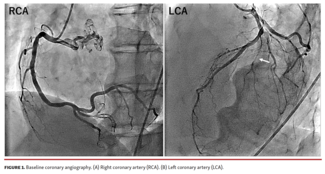

A 59-year-old man with a 95% stenosis in his diagonal branch and no stenosis in the right coronary artery (RCA) or left circumflex artery was scheduled for PCI. This is the first reported case that combined 2 variants of KS in a single...